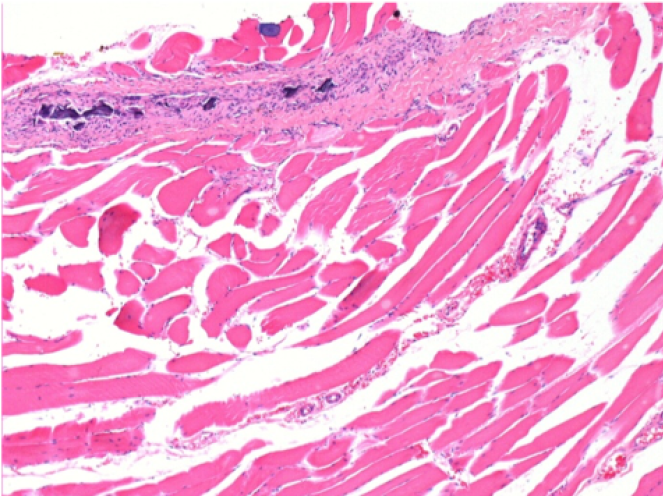

Endopeel Injection in Subcutaneous Tissue

0.5 ml ( 5x 0.1ml) Endopeel SC Injection in the right subcutaneous pretibial area.

L:200x-Control-SC

R-D10-SC-200X

R-D30-SC-200X

R-D90-SC-200X

R-D210-SC-200X

R-D210-SC-400X

- Endopeel induces a selective reversible myofibrolysis and inflammatory reaction on a period of 1 month, approximately

- Muscular changes are reversible in almost full totality

- The muscle is the better place to inject Endopeel because of more efficacity, control and duration of its action

- No necrosis nor abcess have been found all over the study.